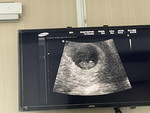

ท้องได้ 9 สัปดาห์ น่าจะเกือบจะ 10 สัปดาห์แล้ว รู้สึกคันบริเวณช่องคลอดมากเลยค่ะ มีแม่ๆ ท่านไหนเป็นเหมือนกันมั๊ยค่ะ ควรไปหาหมอมั๊ย

กำลังตั้งครรภ์